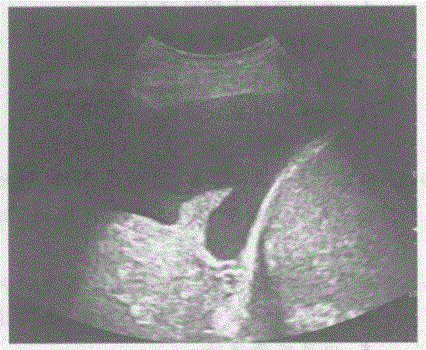

问题 临床资料:男,46岁,自述呛咳、胸闷、进行性呼吸困难两周余。CT:右肺转移癌,肺不张。 超声综合描述:坐位背部右侧胸腔扫查右肩胛线一右腋前线第8肋间以下可见大片状无回声区,深度7.0cm,距体表2.3cm,内透声清亮,无回声内见细长楔形中等回声区漂浮。 超声提示:

选项 A.右肺囊性占位 B.右侧胸腔包裹性积液右肺下叶不张 C.右膈下积液 D.右侧胸腔大量积液右肺下叶不张

答案 D